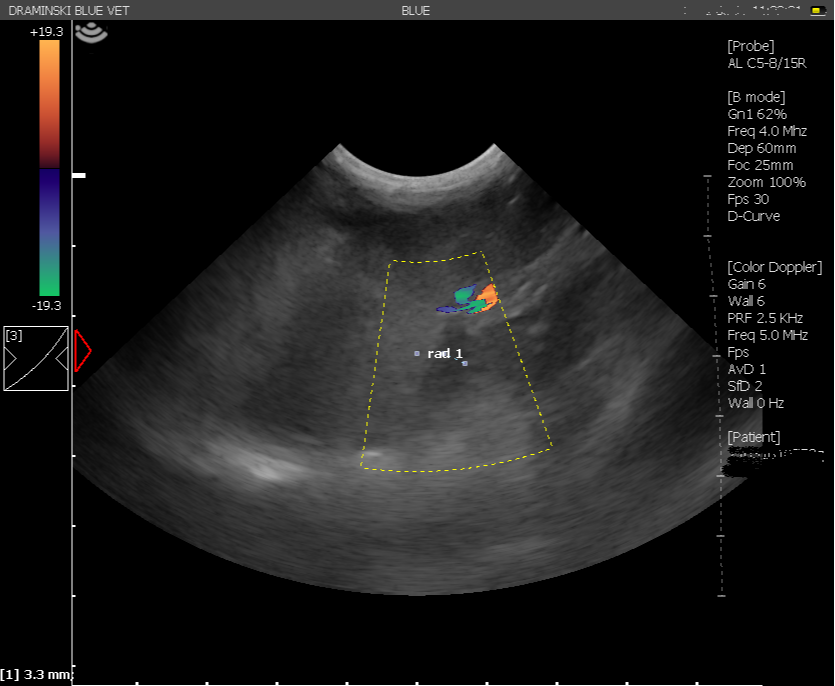

The image quality was good, and I was really impressed that power Doppler was available on a machine at this price. I found navigating the machine really easy – everything is so well labelled – it’s hard to go wrong! The machine is very easy to move around with it’s inbuilt handle and sets up very quickly – it really maximises space versus screen size well.

Images from the Blue